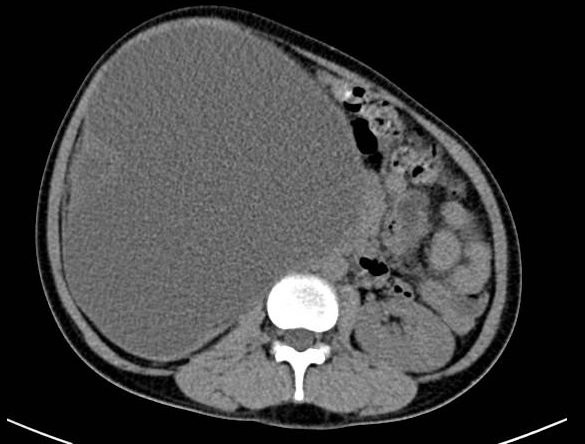

| Hình ảnh cắt lớp vi tính của bệnh nhân M. trước lúc phẫu thuật. Ảnh: BVĐKQT |

Quá trình thăm khám kết hợp với kết quả xét nghiệm, siêu âm và chụp cắt lớp vi tính ổ bụng, các bác sĩ phát hiện thận bệnh nhân bị ứ nước độ 4 do sỏi niệu quản (nhu mô thận chỉ còn như tờ giấy) kèm theo triệu chứng nhiễm trùng. Bệnh nhân M. được chẩn đoán thận phải ứ mủ độ 4, mất chức năng.